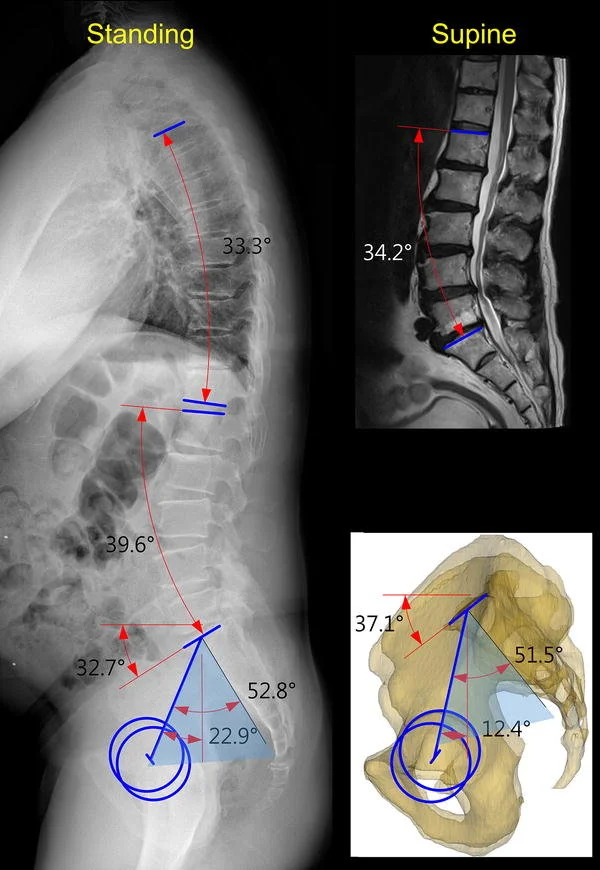

Η χειρουργική παραμόρφωσης είναι από τα διορθωτικές επεμβάσεις με τον μεγαλύτερο προεγχειρητικό σχεδιασμό. Η απεικόνιση και οι μετρήσεις καθορίζουν τους στόχους, τις οστεοτομίες και το πλάνο σταθεροποίησης.

- Ακτινογραφίες ολόκληρης της σπονδυλικής στήλης σε όρθια θέση (full-length, προσθιοπίσθια & πλάγια), με ισχία/γόνατα σε έκταση και τα πόδια στο άνοιγμα των ώμων, για εκτίμηση της συνολικής ευθυγράμμισης.

Ποιες είναι οι βασικές μετρήσεις (Α7 κάθετος οβελιαίος άξονας, PI, PT, SS, LL) και τι σημαίνουν;

Οι σπονδυλοπυελικές μετρήσεις δεν είναι «ακτινολογικοί αριθμοί». Είναι ο τρόπος να ορίσουμε ρεαλιστικούς στόχους διόρθωσης που θα ταιριάζουν στην εμβιομηχανική του κάθε ασθενούς.

- Α7 κάθετος οβελιαίος άξονας: δείκτης οβελιαίας ισορροπίας (πόσο μπροστά/πίσω είναι «λυγισμένος» ο κορμός).

- Pelvic Incidence (PI): ανατομική παράμετρος της λεκάνης (παραμένει σταθερή για τον κάθε ασθενή, δεν μπορεί να μεταβληθεί).

- Pelvic Tilt (PT): δυναμική παράμετρος «αντιστάθμισης» (πόσο γυρίζει η λεκάνη προς τα πίσω για να αντιρροπήσει την παραμόρφωση). Ιδανικά στοχεύουμε < 25°, ανάλογα με το προφίλ ασθενούς.

- Sacral Slope (SS): κλίση ιερού, σχετίζεται με την οβελιαία στάση.

- Lumbar Lordosis (LL): οσφυϊκή λόρδωση. Ένας κλασικός στόχος αποκατάστασης της συνολικής ισορροπίας είναι: LL ≈ PI ± 10°.

Σε καλά ισορροπημένη σπονδυλική στήλη, η σχέση PI–LL βοηθά να αποφύγουμε υπερ- ή υποδιόρθωση. Όταν υπάρχει απώλεια λόρδωσης, ο ασθενής αυτόματα αυξάνει το PT (οπίσθια κλίση λεκάνης) για να «αποκαταστήσει» την ανισορροπία στην όρθια στάση — όμως αυτό έχει λειτουργικό κόστος, συνεχή πόνο και κόπωση κατά τη βάδιση.